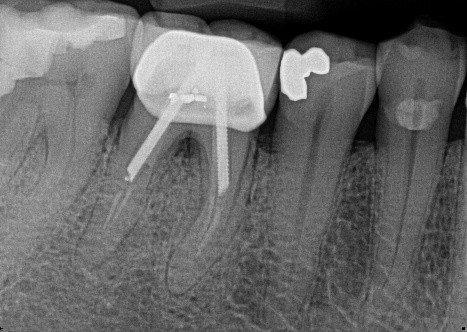

8. (Select ONE OR MORE correct answers)

Which of the following describe(s) the endodontic treatment of tooth 3.6?